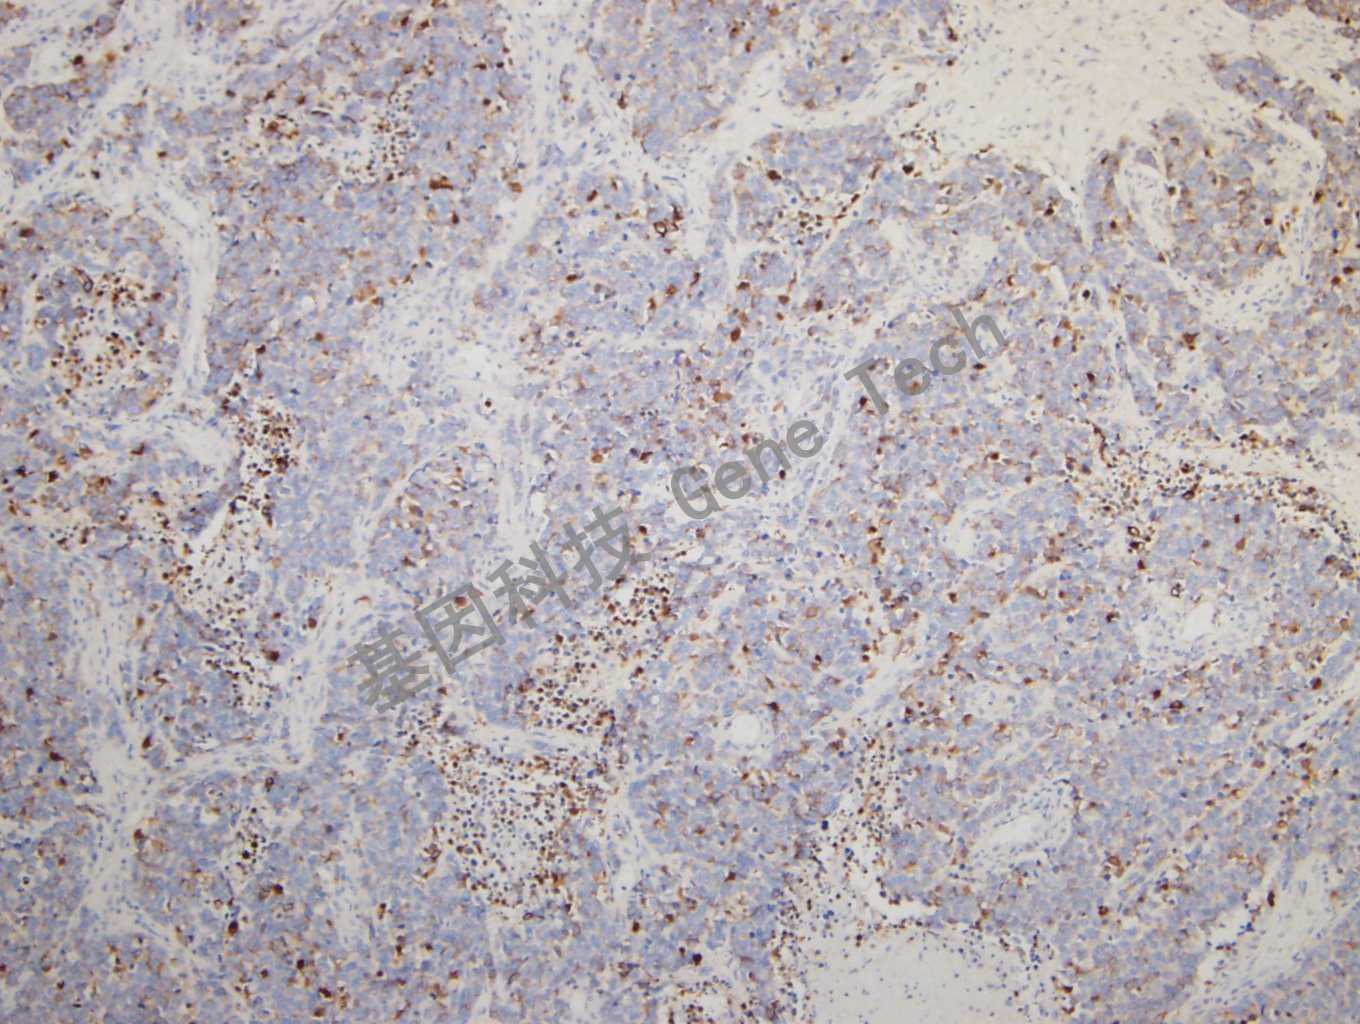

小细胞肺癌石蜡切片,用 CK,pan(GM3515)染色,细胞浆阳性,DAB 显色。